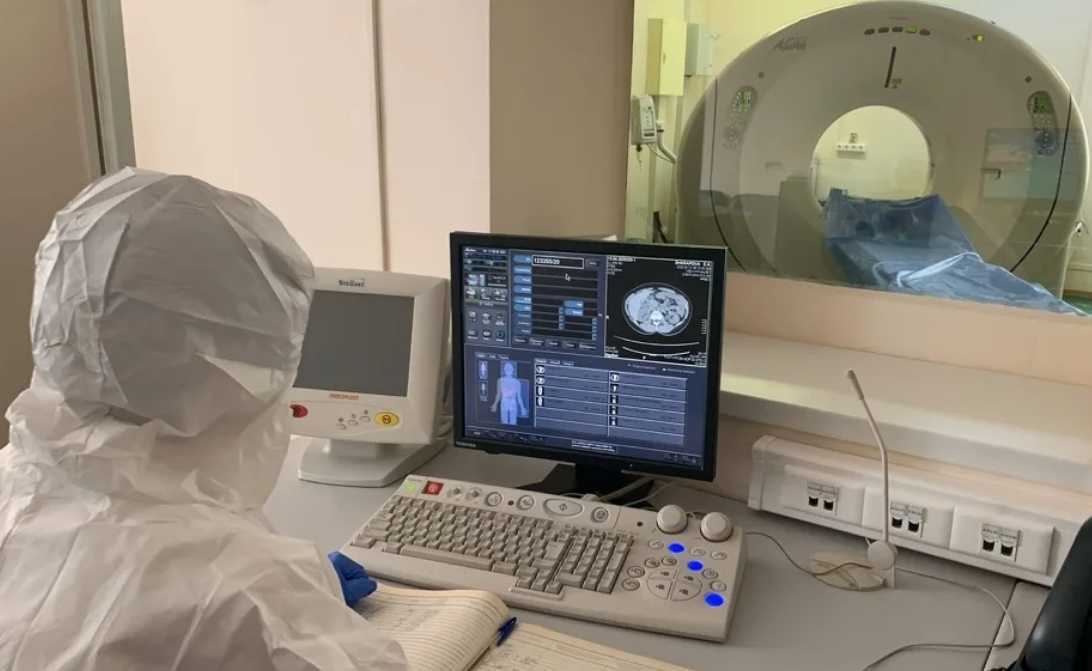

КТ и коронавирус

Обследование посредством КТ часто сегодня назначается при коронавирусе. Что это дает и почему тест рекомендуется Минздравом, вполне объяснимо. Он несет большую пользу при выявлении осложнения у больного COVID-19 — воспаление легких. Компьютерная томография относится к золотому стандарту диагностики состояния легких. Почему именно она рекомендуется при таком диагнозе и подозрении на атипичную вирусную пневмонию:

КТ позволяет определить наличие пневмонии из-за коронавируса на ранних стадиях, а иногда при отсутствии характерных симптомов. Более точного метода выявления атипичной пневмонии на сегодня не существует.

При этом нельзя упускать тот факт, что симптомы коронавируса нарастают быстро. И чем раньше будет проведена компьютерная томография, тем лучше. Если это обследование сразу показывает типичные признаки, то у специалистов практически не остается сомнений. Больному назначают противовирусное лечение даже тогда, когда ПЦР не подтвердил диагноза.